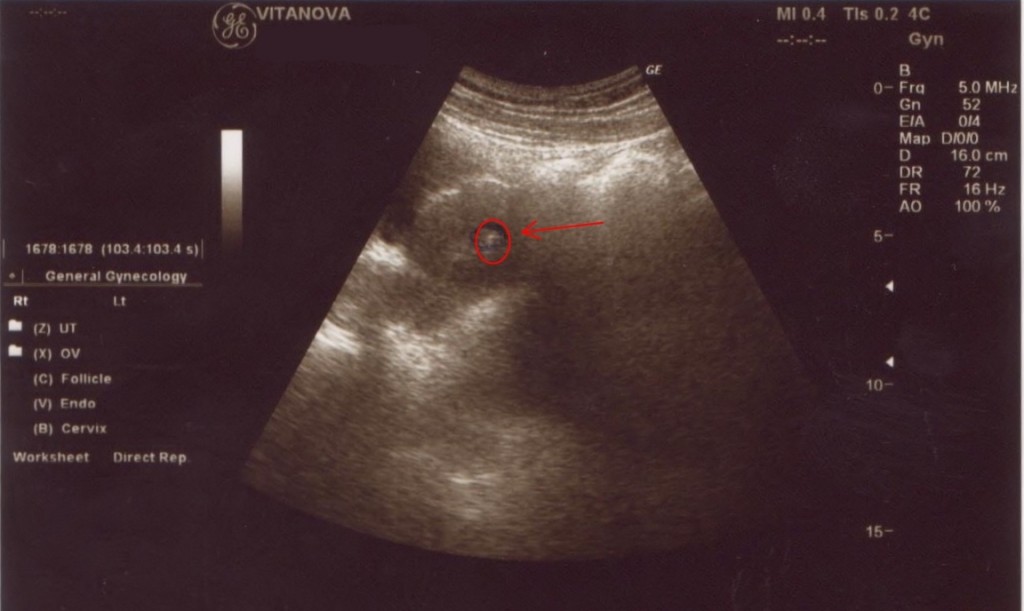

Fasi dell'impianto dell'embrione